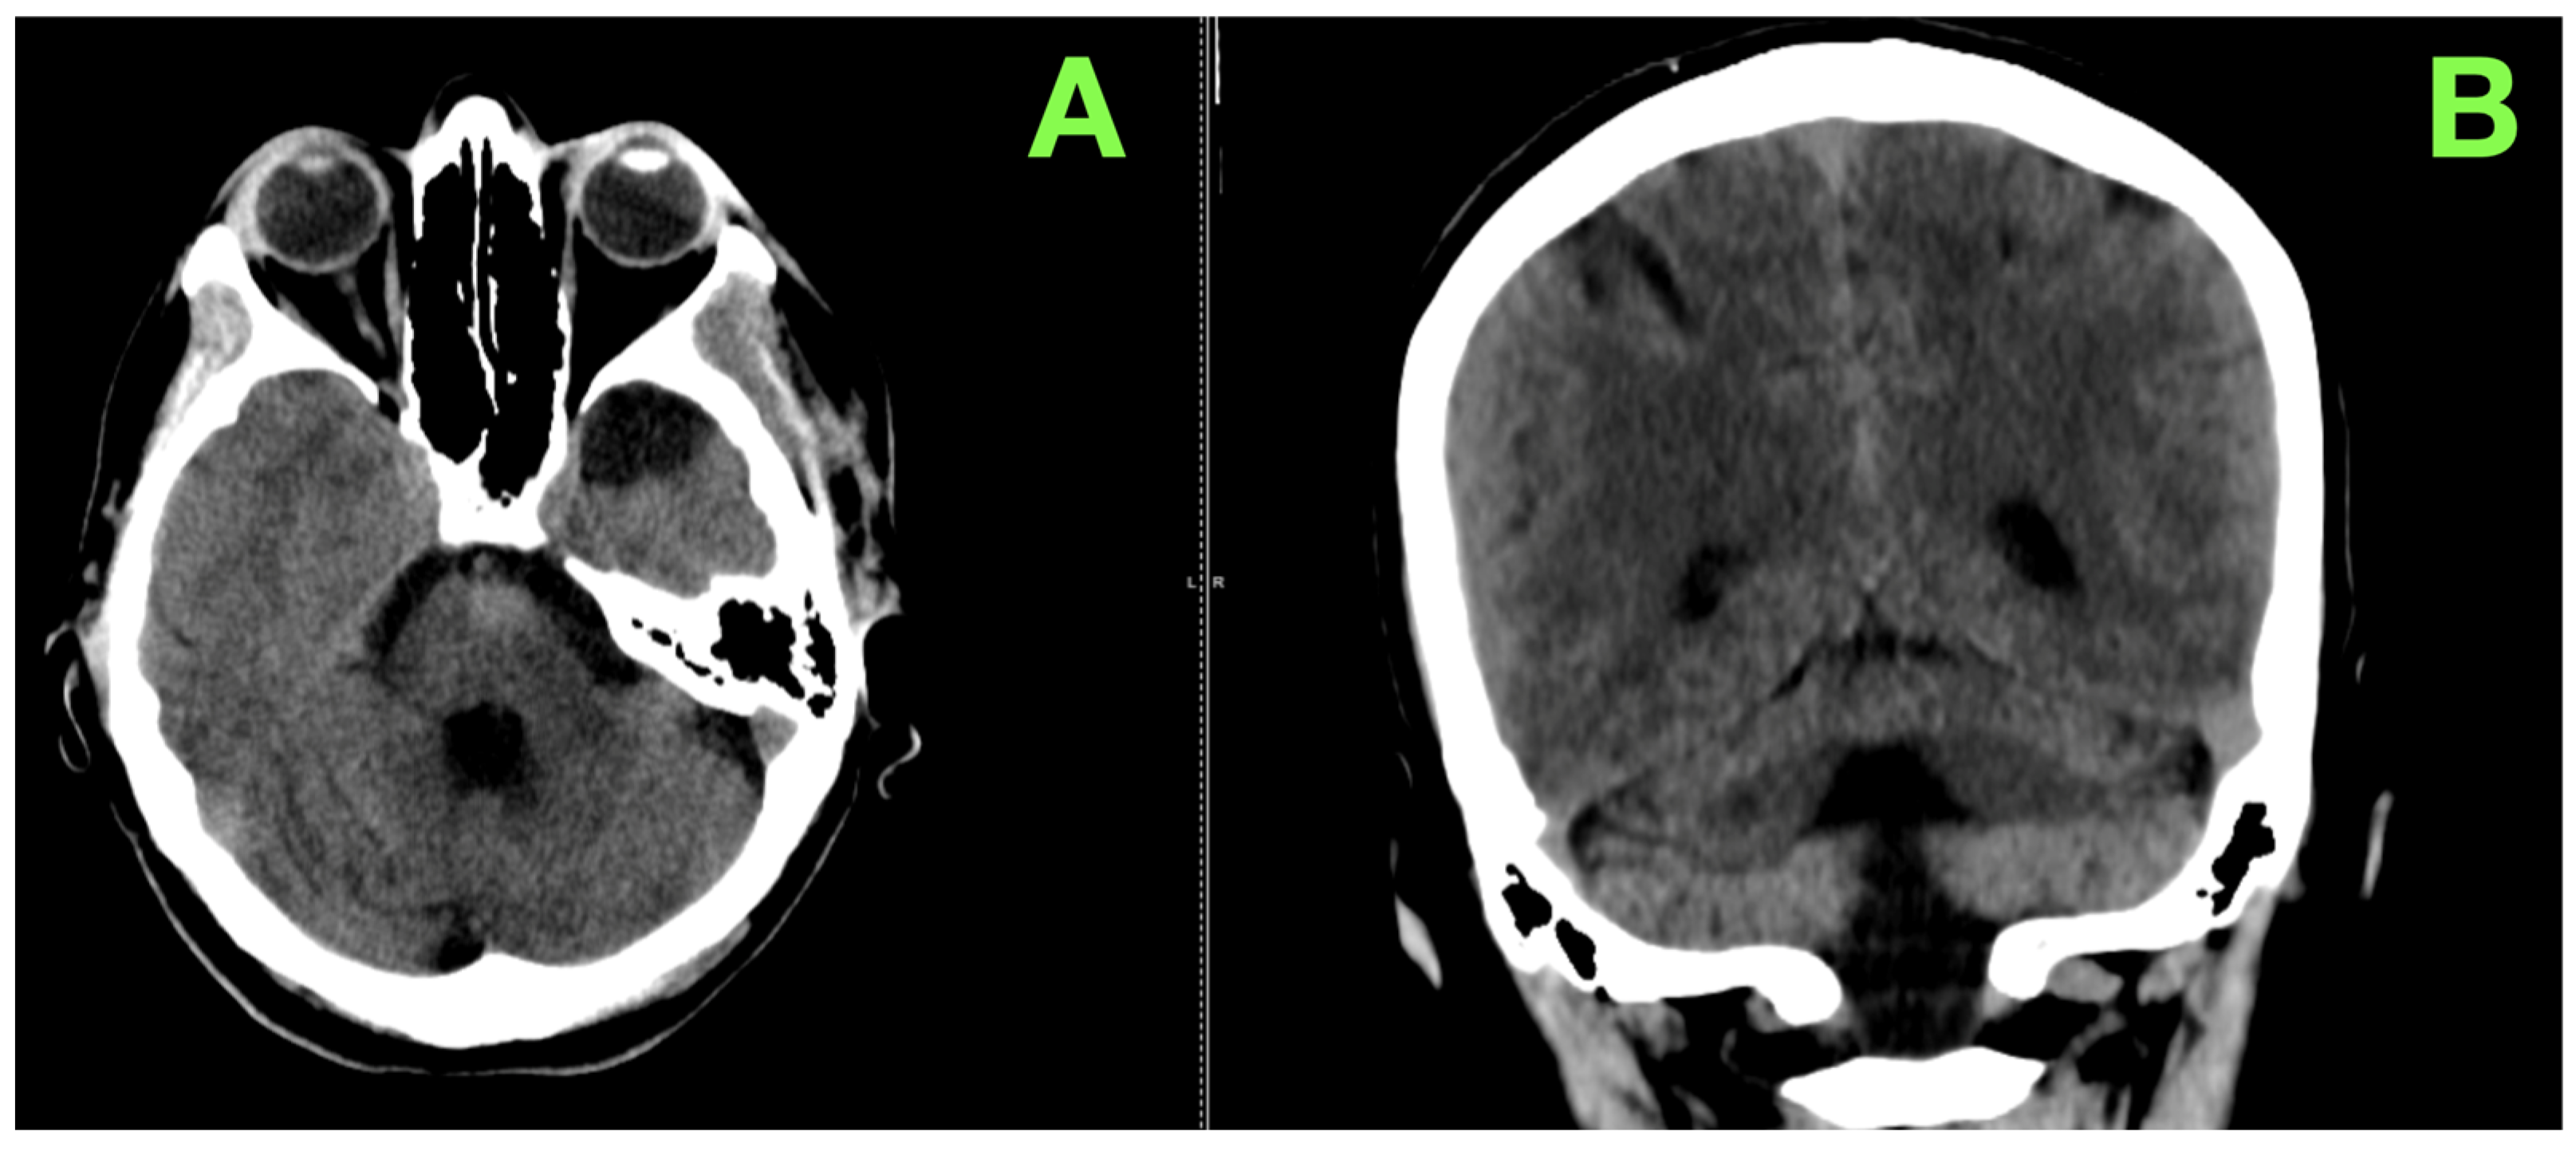

2. Case Presentation